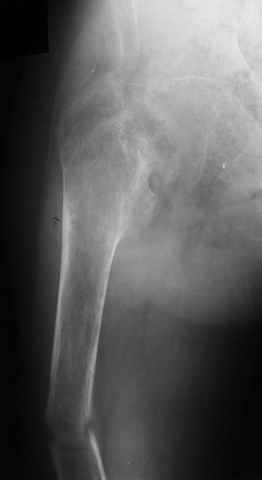

Subject: Osteoporotic Femur Fx

A male 23 y.o. many years sustained severe osteoporosis with multiple fractres of long bones and ribs. Last 4 years was not able to leave chair. Some x-rays attached. What may cause the situation? Juvenile osteoporosis should have been recovered spontaneously to date. What lab research is needed? What is most likely diagnosis? Can such fractures be treated more aggressively? What medications can improve bone quality? Biphosphonates? Somatotropin?